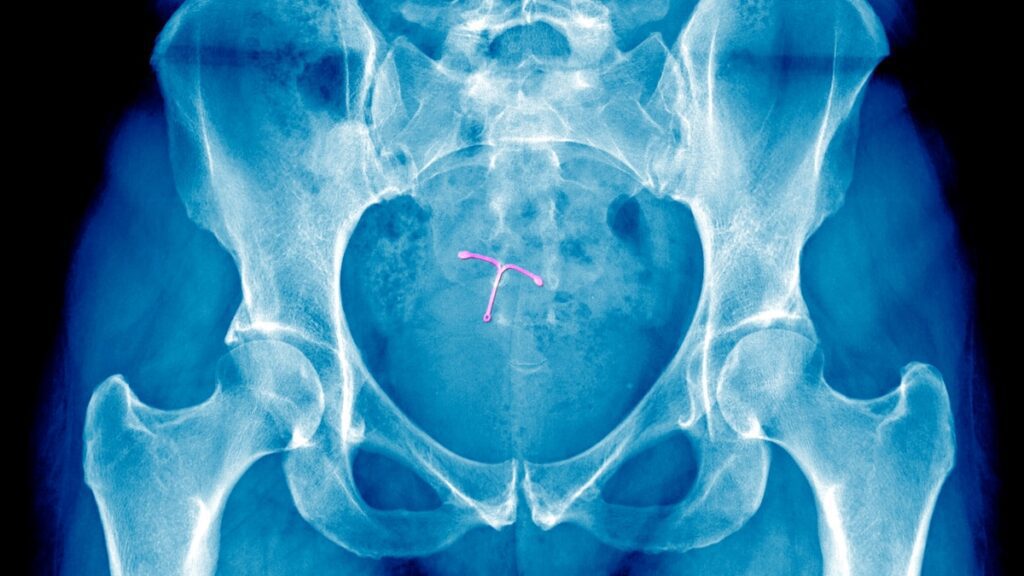

The complexity of pain management is further exacerbated by research that has produced mixed results regarding various strategies. Real-world scenarios often yield unpredictable outcomes. For instance, King reflects on her experience, stating, “When I had an IUD placed with a cervical block, it didn’t help at all. It was exceedingly painful.”